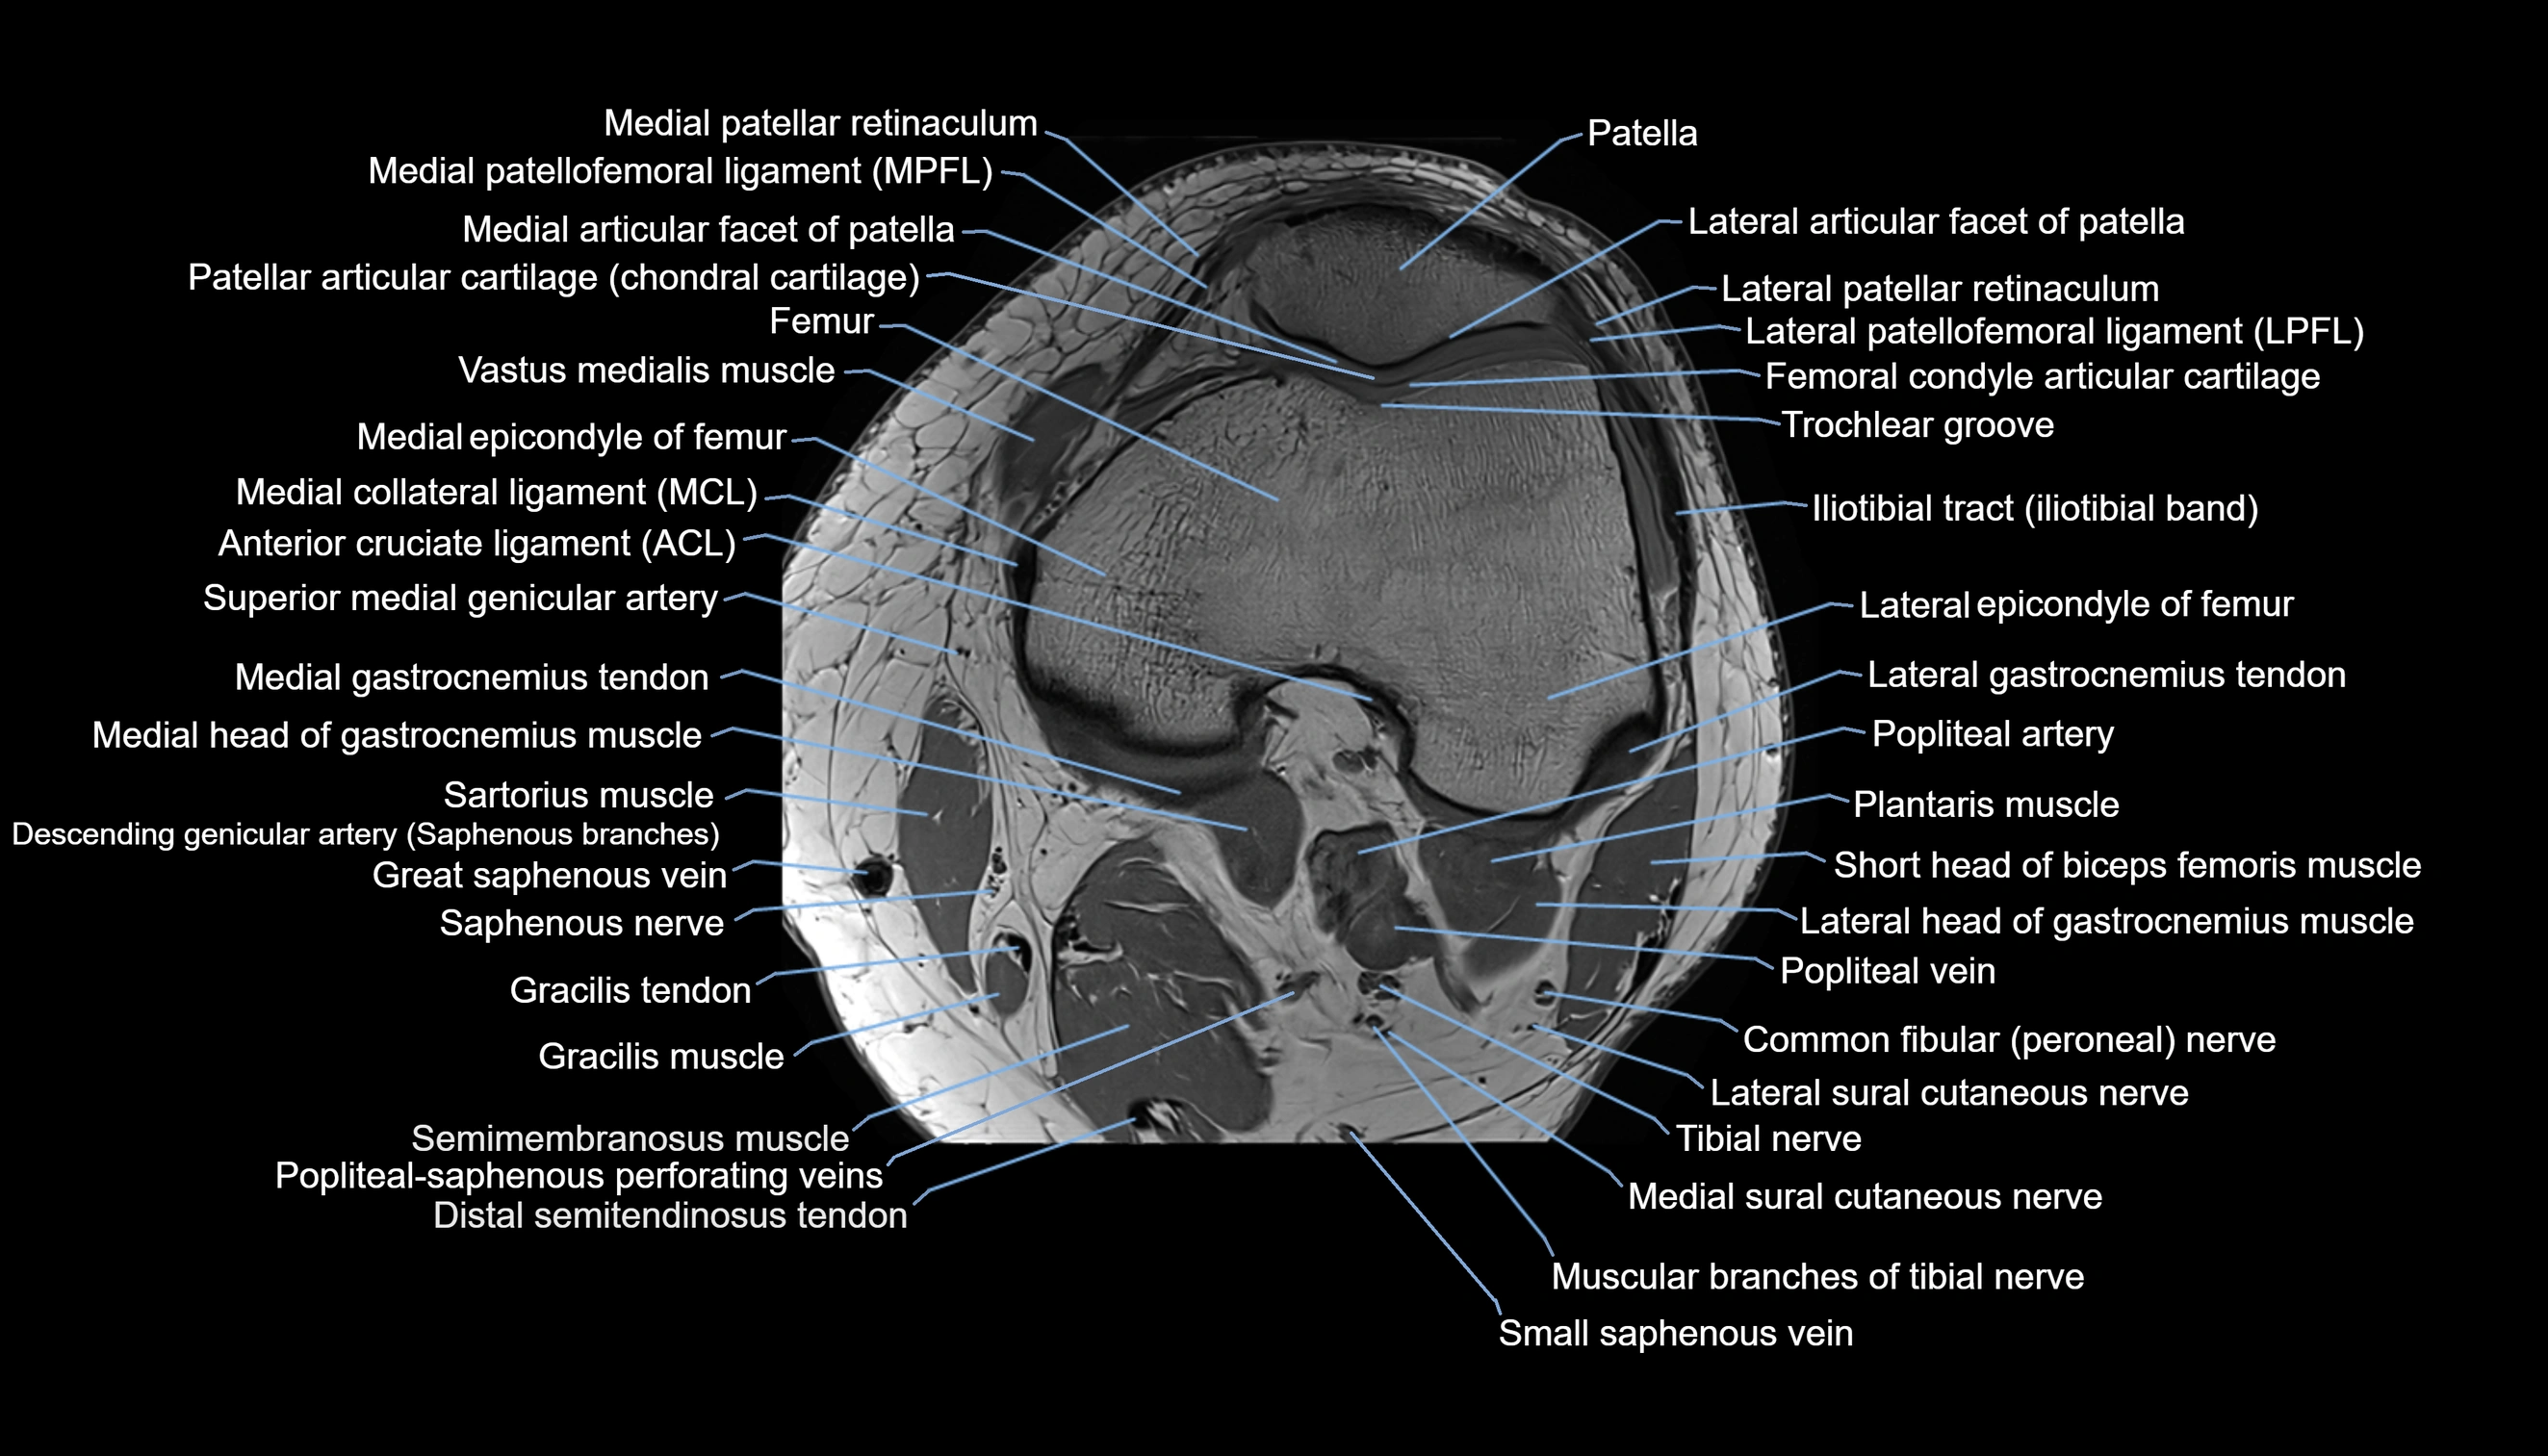

- Knee Joint

- Lateral articular facet of patella

- Lateral border of patella

- Lateral patellar retinaculum

- Lateral patellofemoral ligament

- Medial articular facet of patella

- Medial border of patella

- Medial collateral ligament

- Medial epicondyle of femur

- Medial gastrocnemius tendon

- Medial head of gastrocnemius muscle

- Medial patellar retinaculum

- Medial patellofemoral ligament

- Medial sural cutaneous nerve

- Medial tibial plateau

- Muscular branches of tibial nerve

- Patella

- Patellar articular cartilage

- Popliteal artery

- Popliteal vein

- Saphenous nerve

- Sartorius muscle

- Semimembranosus muscle

- Small saphenous vein

- Superior medial genicular artery

- Tibial nerve

- Vastus medialis muscle

- great saphenous vein